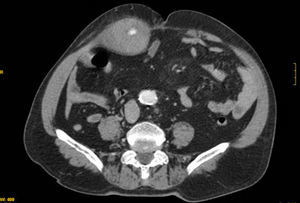

Para descartar una enfermedad retroperitoneal se realizó una TAC abdominal (fig. 2), en la que se observó un voluminoso hematoma a nivel del músculo recto anterior del abdomen derecho, con una longitud máxima de 24cm.

El diagnóstico se confirma con la realización de una ecografía o una TC abdominal con una elevada sensibilidad6,10, aunque el punto más importante es pensar en esta dolencia y realizar una correcta anamnesis y exploración del paciente5. En la ecografía se observa una lesión ocupante de partes blandas, heterogénea, con áreas hipoecoicas que alternan con áreas hiperecoicas, y en la TC, una masa de partes blandas contenida dentro del músculo, homogénea o heterogénea; en caso de que exista hemorragia activa podemos detectar el punto sangrante con la administración de contraste intravenoso.